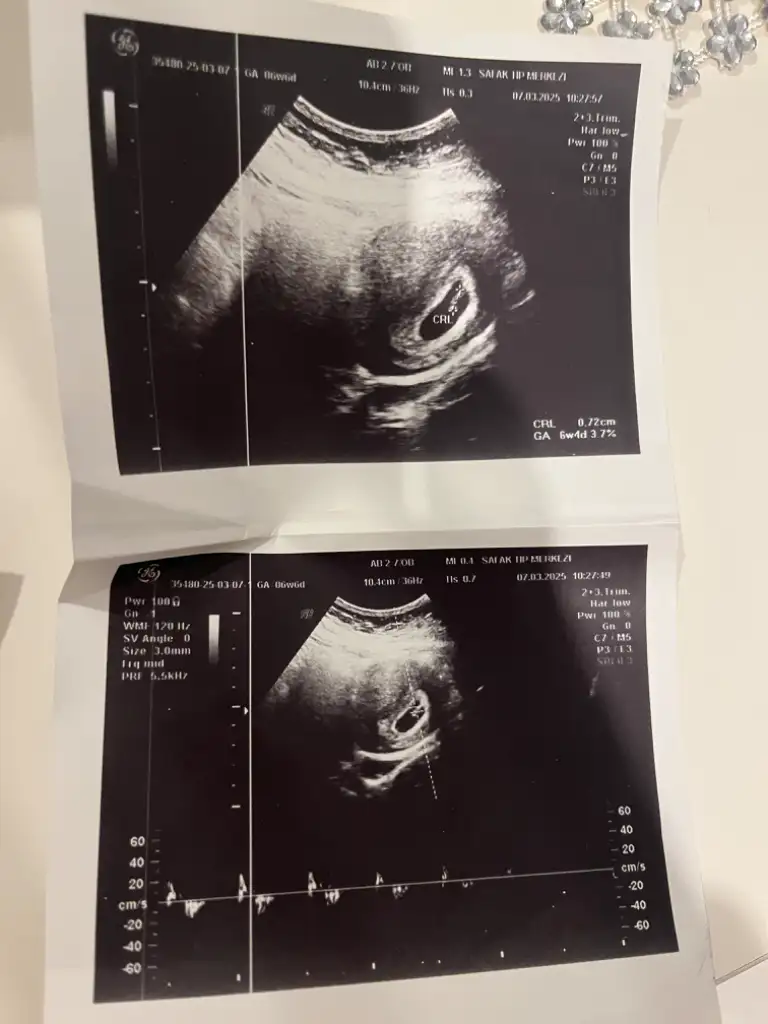

Bana da yorum yapabilir misiniz kızlar 7. Haftadan abdominal goruntu

• IMG_3201.webp

IMG_3201.webp

40,9 KB · Görüntüleme: 58

• IMG_3202.webp

IMG_3202.webp

50 KB · Görüntüleme: 70

Abdominal görüntüyse eğer kız olabilir ☺️🌸 ama sanki sizin ultrason görüntünüz ters gibi . Normalde dar olan kısım yukarda geniş olan kısım aşağıda olur. Bilemedim bu bebişe karar vermek zor çünkü görüntü tam tersiyse eğer erkek de olabilir ☺️ sağlıkla gelsin. Daha net bir görüntü olursa paylaşın ☺️